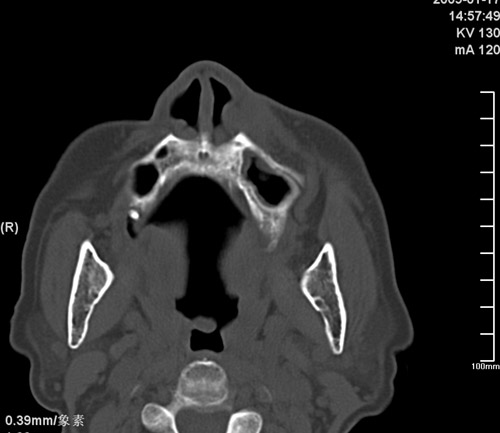

标题: CT17755:女,74 左鼻旁肿胀半年,临床以左上颌窦旁占位行CT [打印本页]

标题: CT17755:女,74 左鼻旁肿胀半年,临床以左上颌窦旁占位行CT

ct考虑鼻前庭囊肿 或鼻翼基底部慢性炎症,左上颌窦少许炎症 请指教

1)考虑左侧鼻前庭囊肿并感染。2)双侧上颌窦炎。

左侧鼻前庭囊肿并感染。双侧上颌窦炎。支持